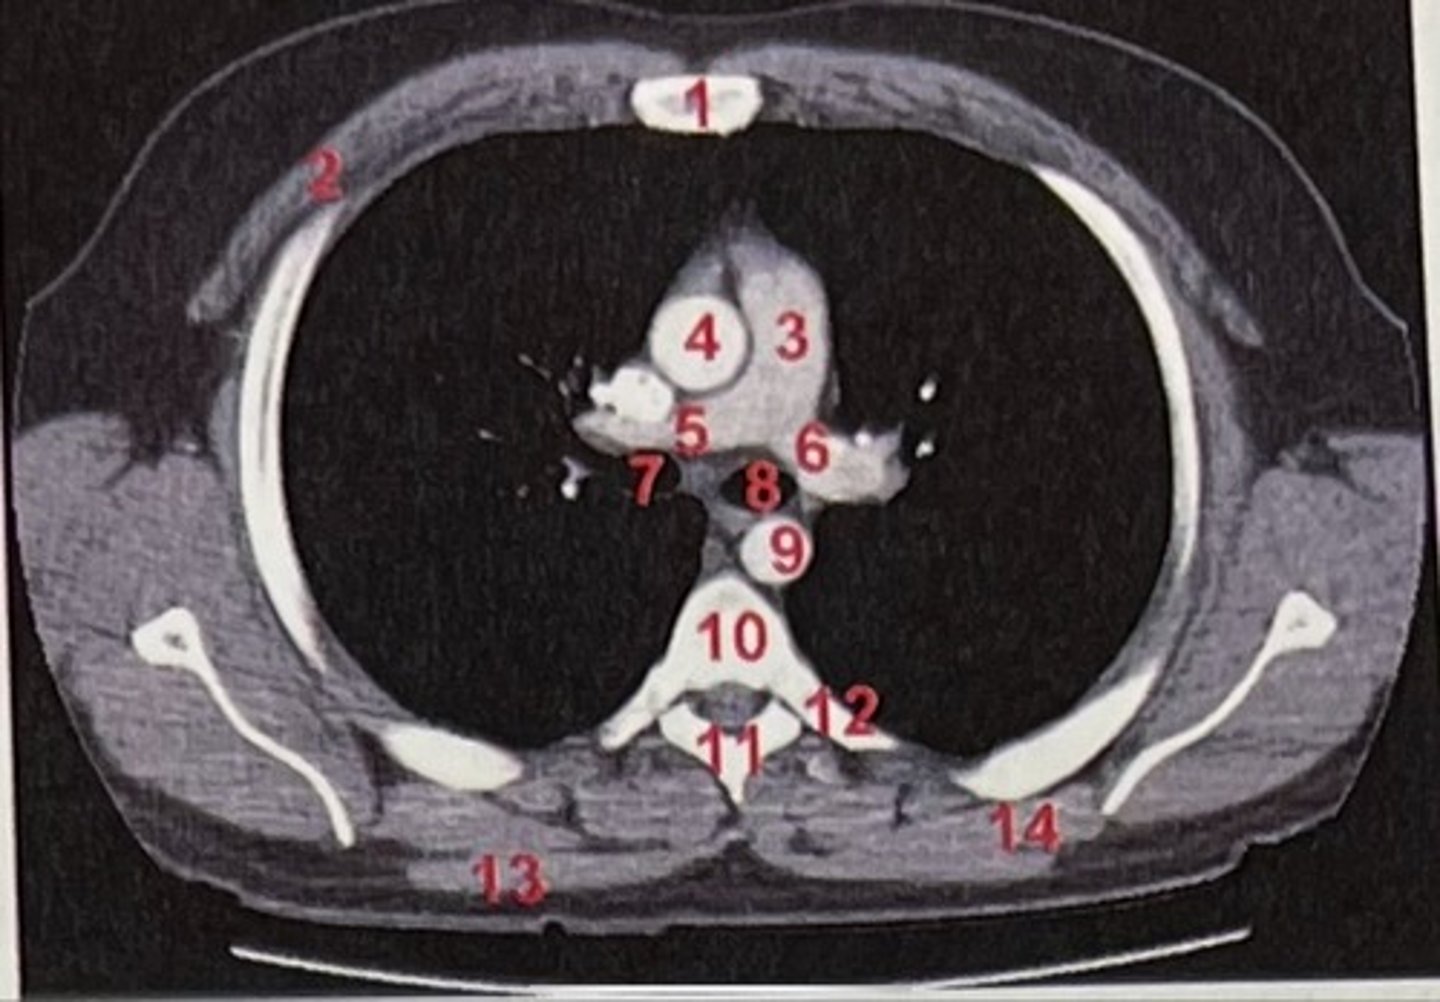

Sternum

What is 1

pectoralis major

What is 2

Pulmonary trunk

What is 3

Right and left pulmonary arteries

What is 5 and 6

Ascending aorta

What is 4

right primary bronchus, left primary bronchus

What is 7 and 8

Descending aorta

What is 9

Rhomboid major

What is 14